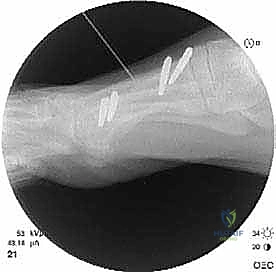

* الأشعة السينية العادية (X-rays) أثناء الوقوف: هذا هو الفحص الأهم. يتم أخذ صور للقدمين أثناء تحمل الوزن لقياس زوايا العظام بدقة، وتحديد مقدار النقص في طول مشط القدم الأول مقارنة بالثاني (يجب أن يكونا متقاربين في الطول ضمن نسب محددة).

* التصوير المقطعي المحوسب (CT Scan): يُطلب في الحالات المعقدة لتقييم جودة العظم المتبقي والتخطيط الدقيق للقص الجراحي ثلاثي الأبعاد.

الخطوة الثالثة: قص العظم (Osteotomy)

باستخدام منشار جراحي ميكروسكوبي دقيق، يقوم الدكتور هطيف بقص عظم مشط القدم. تعتمد زاوية وشكل القص (مثل القص المائل أو القص على شكل حرف Z) على مقدار الإطالة المطلوبة وشكل العظم المتبقي من الجراحة السابقة.

الخطوة الخامسة: التثبيت الداخلي القوي (Internal Fixation)

لضمان التئام العظم في وضعه الجديد والطويل، يجب تثبيته بقوة شديدة. يستخدم الدكتور هطيف أحدث الشرائح المعدنية التيتانيوم ذات الزاوية الثابتة (Locking Plates) والمسامير الدقيقة. هذا التثبيت القوي يمنع أي حركة بين العظام ويسمح ببدء العلاج الطبيعي في وقت مبكر.